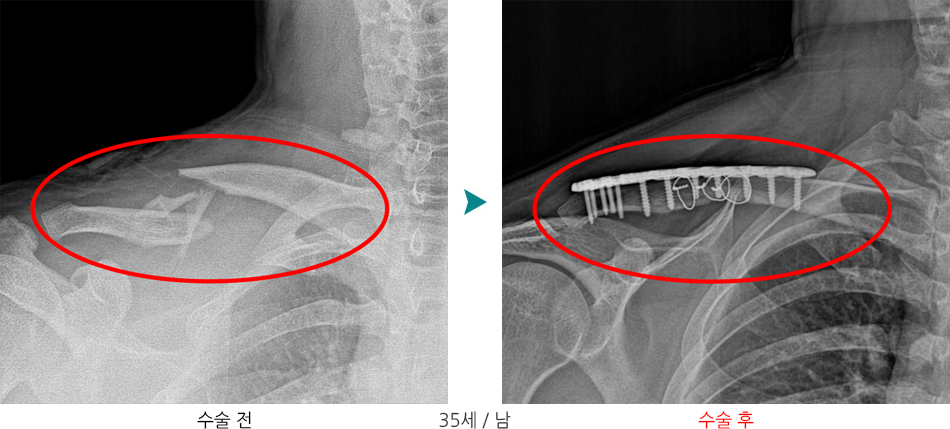

쇄골(clavicle)은 흉골(sternum)과 견갑골(scapula)을 연결하는 S자 모양의 긴 뼈로, 어깨의 위치를 유지하는 데 중요한 역할을 합니다.

골막이 두껍고 혈류가 풍부하지만, 중간 1/3 부위는 얇고 약해 골절이 가장 잘 일어납니다.